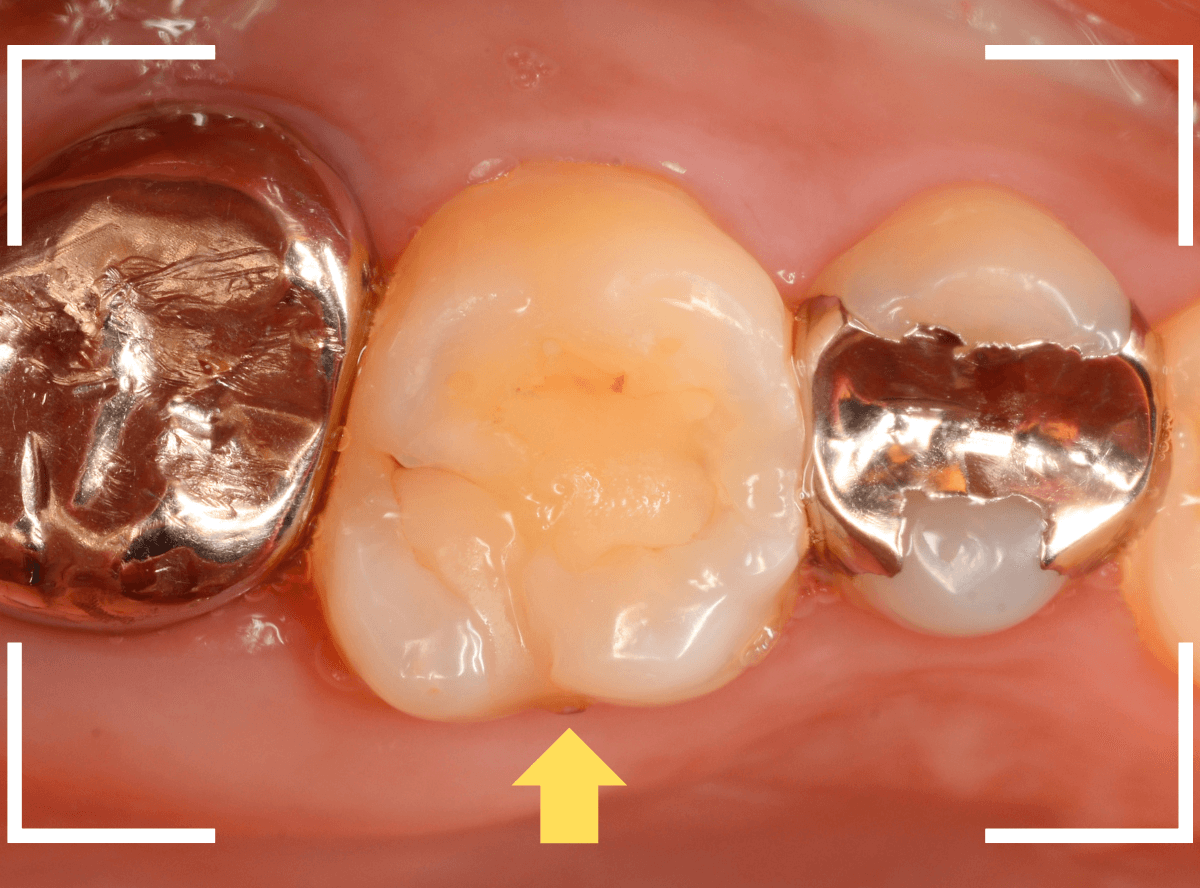

Case.14 噛むと上の奥歯が痛い

「噛むと上の奥歯が痛い」という症状で来院された患者さんです。

打診(ピンセットなどで歯を叩き比べて、痛みの原因の歯を診断する方法)で矢印の歯が痛い事がわかりました。

レントゲン写真で確認します。

レジンの下の赤い色の線が虫歯であろうと思われる部分です。

痛みのある歯については、なんとも微妙な写り方に見え、虫歯だと断言し難い状況でした。

このような場合は、症状とレントゲン写真などから推察していくのですが、痛みは噛んだ時のみで、虫歯特有のしみるなどの症状がないため、そこからも判断しづらい状況でした。

あとは、虫歯と思われる部分を削りながら調べていくしかありません。

患者さんに状況をお話しし、レジンを除去して調べてみると、診断通り、虫歯が出てきました。

虫歯をある程度除去したところです。

まず、一番左の〇部、隣の銀歯との間になにか固いものがはさまっています。

物を噛んだ時に痛むのはこれが原因の気がします。

中央の〇部、赤く染まっている部分は虫歯がまだ除去しきれていない部分です。思ったよりも深めの虫歯です。

一番右の〇部は、メタル・インレーのつけ根に虫歯が小さく顔を出しています。

痛みのある歯の虫歯をすべて除去し、はさまっていた物も全て除去したところです。

手前の歯のメタル・インレーを除去し、虫歯を除去すると、その手前の歯のレジンも不適合なのが見つかりました。

全ての虫歯を除去したところです。

思っていたよりも広い虫歯でした。

しばらくお薬をつめて、経過観察をします。